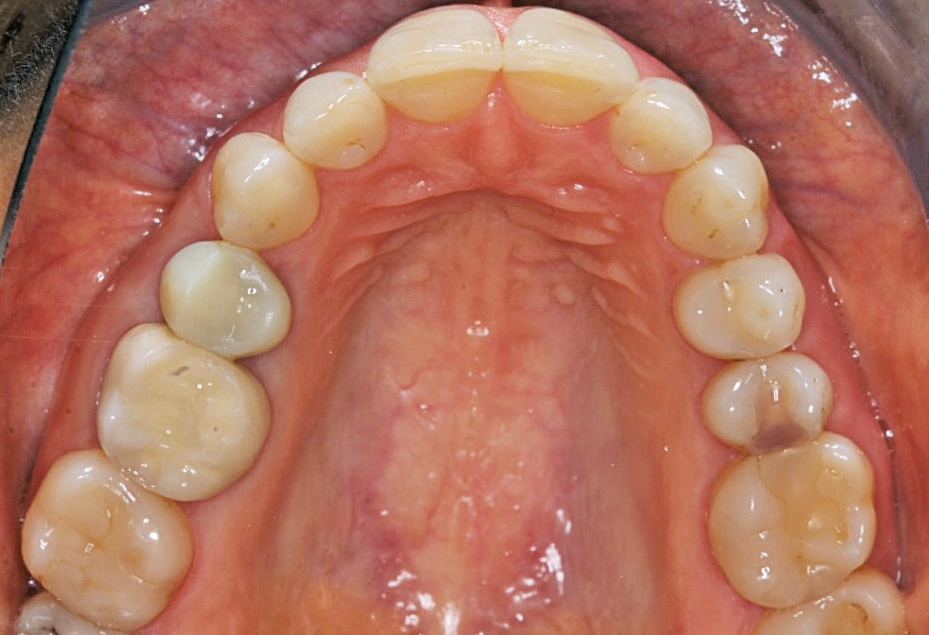

Nach einer komplikationsfreien Einheilzeit von vier Monaten konnte mit der Herstellung des definitiven Zahnersatzes begonnen werden. Hier entschied man sich konsequent für monolithische Kronen aus Lithiumdisilikat, um das Chippingrisiko so gering wie möglich zu halten [12]. Im Zuge der Implantatversorgung wurde nun auch – wie geplant – die metallkeramische Krone an 16 geschlitzt, entfernt und der Stumpf nachpräpariert. Implantatkopf und Zahnstumpf wurden daraufhin zusammen mit A-Silikon analog abgeformt. Für die geschlossene Abformung wurde die Abformkappe (impression.transfer) auf dem Implantatkopf positioniert. Ein deutliches Einrasten signalisierte den lagestabilen Sitz. Für die Modellherstellung rastete das Implantatanalog (lab. replica) ebenso in die integrierte Abformkappe ein. Nach der Herstellung des Meistermodells konnten die beiden Kronen im digitalen Workflow CAD/ CAM-gestützt gefertigt werden. Nach Ausarbeitung, Bemalung und Glasur waren die beiden Kronen für die definitive Zementierung bereit. Die klinische Einprobe der Restaurationen verlief erfolgreich, sodass die Kronen nacheinander mit selbstadhäsivem Befestigungskomposit eingegliedert werden konnten.

Aber auch bei einem nachträglichen Bindegewebstransplantat zur gingivalen Korrektur bietet ein einteiliges, spaltfreies Implantat aus gewebefreundlichem Zirkondioxid womöglich bessere Chancen auf eine zufriedenstellende rote Ästhetik als zweiteilige Titanlösungen. Die Patientin war in diesem Fall mit dem ästhetischen Erscheinungsbild und der Funktionalität ihrer neuen Versorgungen eineinhalb Monate nach der definitiven Eingliederung absolut zufrieden.